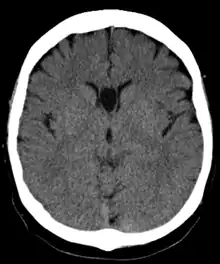

Полость прозрачной перегородки (лат. cavum septi pellucidi) — полость, находящаяся между листками прозрачной перегородки. Полость содержит ликвор, попадающий туда через поры в листках.[1]

Спереди полость ограничена коленом мозолистого тела; сверху — стволом мозолистого тела; сзади — передними ножками и столбами свода мозга; снизу — передней комиссурой и клювом мозолистого тела; латерально — листками прозрачной перегородки.[2]

В большинстве случаев полость не сообщается с полостью желудочковой системы мозга, что делает неправомочным её описание как «5-го желудочка» головного мозга, тем не менее, иногда её называют пятым желудочком.

Собственно полость прозрачной перегородки расположена на уровне основания передних рогов боковых желудочков мозга, а её распространение в заднем направлении в область тел боковых желудочков выделяют под названием полость Верге (лат. cavum vergae). Во время эмбрионального развития происходит закрытие полостей в задне-переднем направлении, из-за чего персистирование полости Верге при закрытой полости прозрачной перегородки встречается значительно реже.